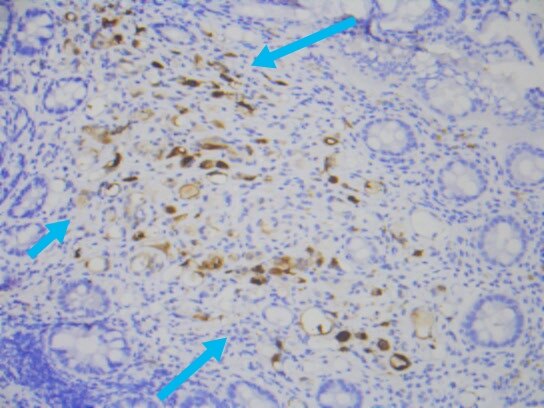

上述免疫组化结果辅助诊断为前列腺腺泡腺癌累及直肠。

加上上述实验室检查,血清psa升高显著,前列腺腺泡腺癌累及直肠就确诊了。所以,老年男性,直肠占位,不能忽视前列腺癌累犯。上述案例,也一再显示癌的发生发展,很长时间内都是静悄悄的,癌可以逃逸人体免疫系统的监控,而疯狂的无序无节制生长,直到破坏了关键器官或组织,才会引起相应的症状。为此,中老年人,规范的健康体检,规范的肿瘤筛查和血清肿瘤标记物的检测,都是十分必要的。当然,我们自己对自己健康的关注才更加重要。了解自己的身体,关注自己的健康,增加健康常识和健康意识都是重要和必需的。